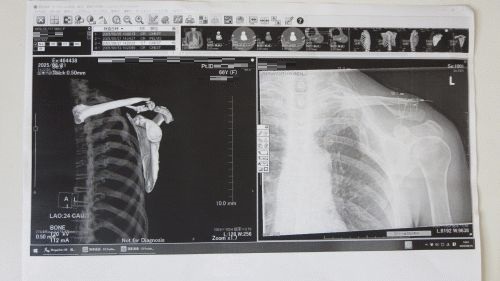

奥様の入院3

国東市民病院へ帰ってきたのは先週です

別府で16日間をベッドで過ごしたため歩くにも介助が必要でした

先日はなんとか歩ける状態にまで回復してました

とは言うもののつぶれた肺の一部は再生しないと聞いてます

加えて肺の内出血はまだ一部残った状態です

骨折部分の手術のリスクとメリット・デメリットなどを説明していただきました

更に、3次元のCT画像とレントゲンの画像を印刷してもらいました

ドクターのわかりやすい説明に感謝です

もう少し入院は続きそうです